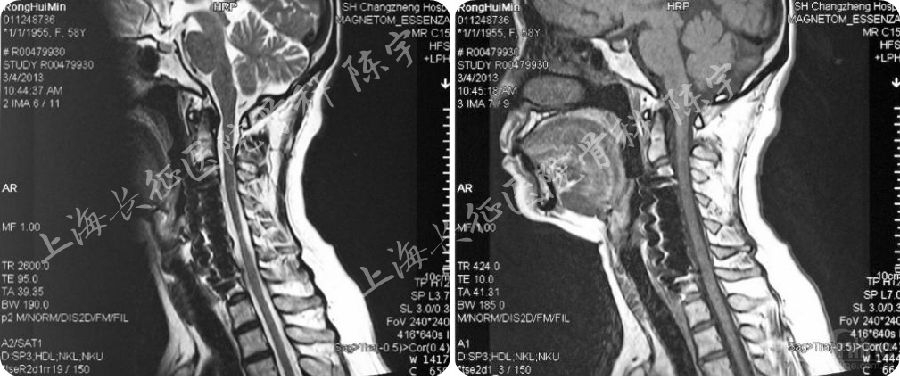

术前影像学检查(图1):

(1) X线:颈椎侧位及伸屈侧位片显示颈椎呈后凸畸形;

(2) MRI:颈4-6水平脊髓严重受压;

(3) CT: 颈4-6连续型后纵韧带骨化,在最严重水平椎管狭窄率达到90%以上,在横断面上表现为典型“双影征”,提示合并硬膜囊骨化。